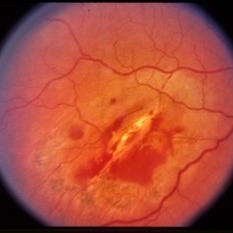

Traumatic posterior subretinal fibrosis.

Condition/keywords: trauma